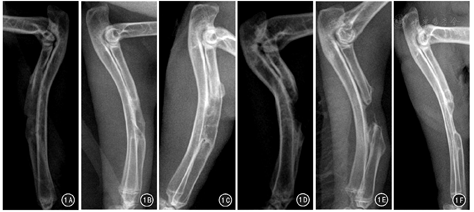

X线图像显示,术后第4周:A1组、A2组桡骨断端有大量不均匀低密度新生骨痂影,且A1组断端基本充满新生骨,A2组桡骨断端尚存在缺损空腔;B1、B2组桡骨断端仅有极少量新生骨生成。术后第8周:A1组桡骨断端有连续性骨痂通过,轮廓欠规则,密度低于正常骨皮质;A2组缺损面积较前稍减小,部分髓腔闭塞;B1、B2组桡骨断端低密度新生骨量增多,缺损空腔面积变化不明显。术后第12周:A1组标本均愈合,髓腔再通;A2、B1、B2组桡骨断端硬化,髓腔闭合,中央为软组织影。见图1、图2。

术后各时间点X线Lane-Sandhu评分显示:组内缺损面积不同的亚组间比较,A1组评分均高于A2组,差异均有统计学意义(P值均<0.05);B1组与B2组评分比较,差异均无统计学意义(P值均>0.05)。组间缺损面积相同的亚组间比较:A1组、A2组评分分别高于B1组、B2组,差异均有统计学意义(P值均<0.05)。见表1。